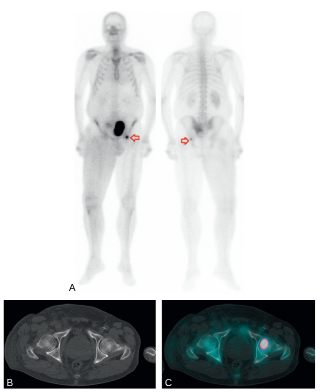

- pour la recherche de métastases osseuses, la scintigraphie osseuse pour le bilan d’extension initial des patients à risque intermédiaire d’Amico en cas de grade 4 majoritaire dans le score de Gleason (figure 30.3) ;

Fig. 30.3 Scintigraphie osseuse. Balayage « corps entier » (A), coupe axiale TDM (B) et coupe axiale TEMP-TDM (C).

Bilan d’extension initial d’un adénocarcinome prostatique (Gleason 4 + 4 avec un taux de PSA à 11,8 ng/ml) retrouvant une hyperactivité ostéoblastique suspecte de lésion secondaire de la tête fémorale gauche (A, flèche rouge).

Source : CERF, CNEBMN, 2022.